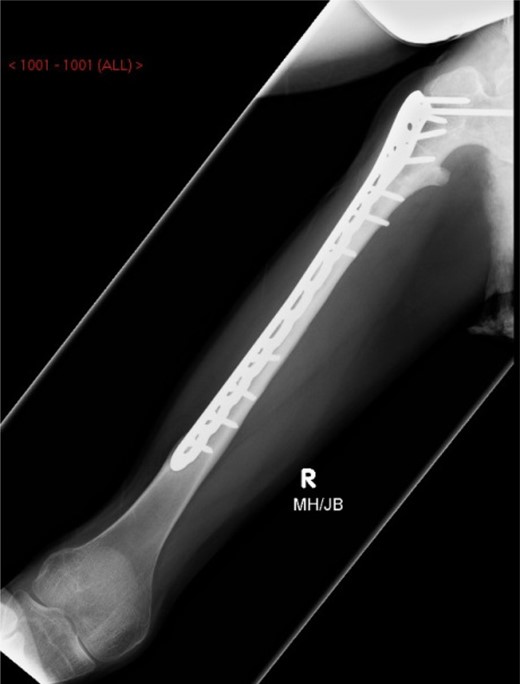

An 18-year-old female with a history of quadriplegic cerebral palsy (GMFCS-V) was admitted to our orthopaedic department following a peri-prosthetic fracture of the right femur. She is well known to our department, as her non-ambulatory status has resulted in a number of surgeries including a right adductor tenotomy, aged 11, femoral derotation osteotomy and dega acetabular osteotomy, aged 13 and right distal hamstring and knee capsule release, aged 14. She presented to the emergency department with a painful right thigh after getting her leg caught in doorway while being mobilized in a wheelchair. The trauma resulted in lateral bending of the leg, with examination revealing a significant deformity of the thigh with audible crepitus. Radiographs revealed a peri-prosthetic fracture of the right femoral shaft extending distal to the AO blade plate (Fig. 1). The blade was also seen to be encroaching on the inferior cortex of the femoral neck leading to concerns about creating a stress riser or femoral neck fracture in the event of revision blade plate fixation. There was also concern that the longest replacement blade plate available would not be of sufficient length to stabilize the fracture distally. The complexity of this case along with the patients low body weight (26 kg), small skeletal morphology and underlying neurological disorder deemed revision with a long-blade plate, or standard adult femoral fixation devices unsuitable. Therefore, we proposed a long PHILOS™ proximal humeral locking plate (Synthes, UK) as a suitable device for internal fixation of the fracture to provide adequate plate osteosynthesis, with secure proximal and distal fixation, bridging the fracture and the femoral neck defect.

AP-XR demonstrating a peri-prosthetic fracture of the right femur below the blade plate. Blade plate noted to be breaching femoral neck.